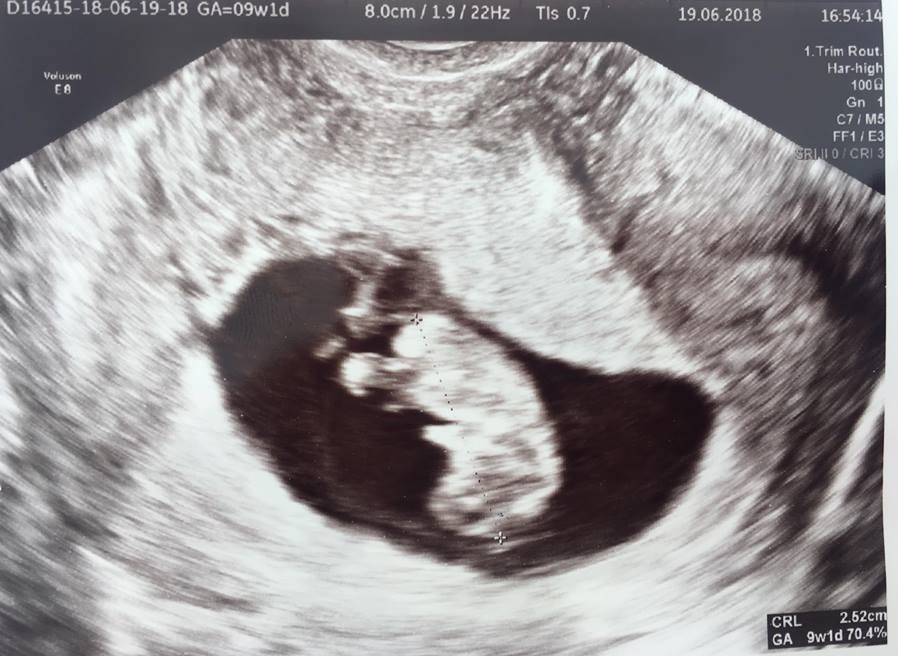

Ja również jestem już po dzisiejszej wizycie. Fasolka ma 2,5 cm i serduszko ładnie bije :) dziwne tylko trochę, że jest głową w dół, ale lekarz powiedział, że wszystko ok.

My po wizycie. Pestka ma się dobrze i rośnie. Ma 1.62cm więc bydlak. Czas określił jako 8 +0 mówiac że to 8 tydz a nie 9?? Dalej leżeć ale można trochę delikatnie zacząć spacerować. Dalej w to nie wierzę.